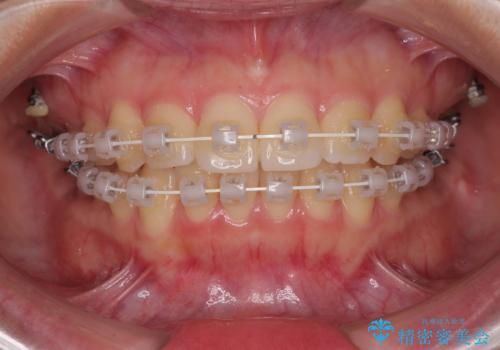

- 矯正装置

- 審美装置

- 治療期間

- 1年1ヶ月

- 治療回数

- 10-30回